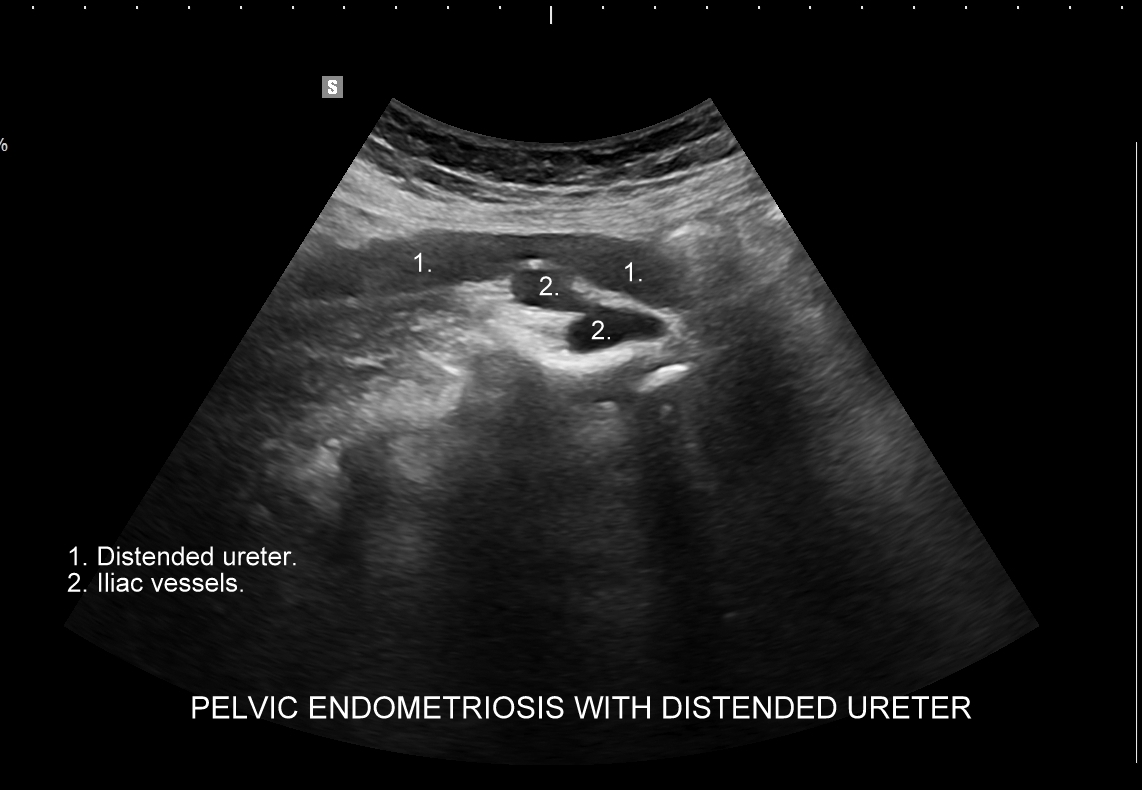

Na skanach w niniejszym artykule zaprezentowany jest przypadek endometriozy głębokiej w miednicy mniejszej z intraluminalnym nacieczeniem dystalnego odcinka moczowodu, jego całkowitą niedrożnością i wtórnym wodonerczem. Choroba w tak zaawansowanym stadium wykryta została przypadkowo w rutynowym przezbrzusznym badaniu USG jamy brzusznej. W ramach diagnostyki różnicowej przeprowadzone zostały badanie CT, MRI oraz ureterocystoskopia z pobraniem materiału do badania histopatologicznego, na podstawie którego postawiono rozpoznanie endometriozy.